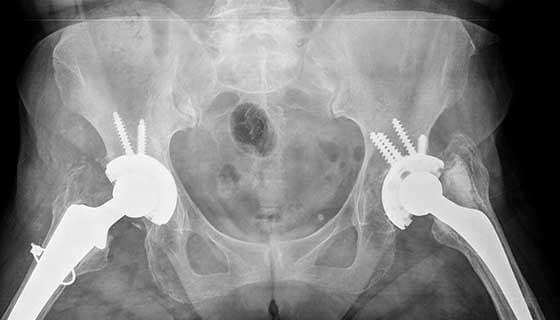

Hip arthroplasty, commonly known as hip replacement surgery, is a surgical procedure designed to replace a damaged or diseased hip joint with a prosthetic implant.

Hip replacement surgery, also known as hip arthroplasty, is a transformative medical procedure aimed at alleviating chronic pain and restoring mobility in patients suffering from severe hip joint damage. This surgery is predominantly performed on individuals affected by osteoarthritis, rheumatoid arthritis, or traumatic injuries that have led to the deterioration of the hip joint. During the procedure, the surgeon removes the damaged cartilage and bone from the hip joint and replaces it with prosthetic components made of metal, ceramic, or high-density plastic. The prosthetic joint is designed to replicate the natural movement of the hip, allowing patients to regain a significant degree of function and mobility.

There are two main types of hip replacement surgery: total hip replacement (THR) and partial hip replacement. In a total hip replacement, both the acetabulum (the hip socket) and the femoral head (the ball of the thigh bone) are replaced. In a partial hip replacement, only the femoral head is replaced. The choice between these procedures depends on the patient's specific condition and the extent of joint damage.

Total hip replacement (THR), on the other hand, involves replacing both the femoral head and the acetabulum with prosthetic components. This comprehensive approach is often necessary for individuals suffering from severe osteoarthritis, rheumatoid arthritis, or other degenerative conditions that affect both parts of the hip joint. During a total hip replacement, the surgeon removes the damaged cartilage and bone from both the femoral head and the acetabulum, replacing them with artificial components made of metal, ceramic, or plastic. The prosthetic components are designed to mimic the natural movement of the hip joint, providing significant pain relief and improved mobility.